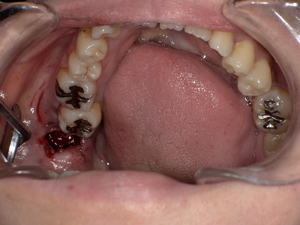

口の中に白っぽい「線状・網目状・斑点状」の病変が現れ、粘膜が硬く、時に痛みやヒリヒリ感、赤みを伴います。病変部がむずがゆい、物を噛むときに不快感がある、口内炎が繰り返すような感覚が現れる方も多いです。

口の中のどこにできる?(舌・頬・歯茎など)

頬の内側:もっとも一般的。

舌の横や裏:白斑が見られやすいです。

歯茎や唇の裏:発生することもあり、視認しづらいため注意が必要。

口腔扁平苔癬の主な症状|痛み・赤み・白斑などの見分け方

初期:細かい白い網目状、軽度のかゆみや違和感

中期〜進行期:白板形成、赤み、潰瘍、強い痛み、出血などが出ることもあります。

医師の視診で典型的な白斑や網目状の模様が観察されれば、口腔扁平苔癬と仮診断されることが多いです。